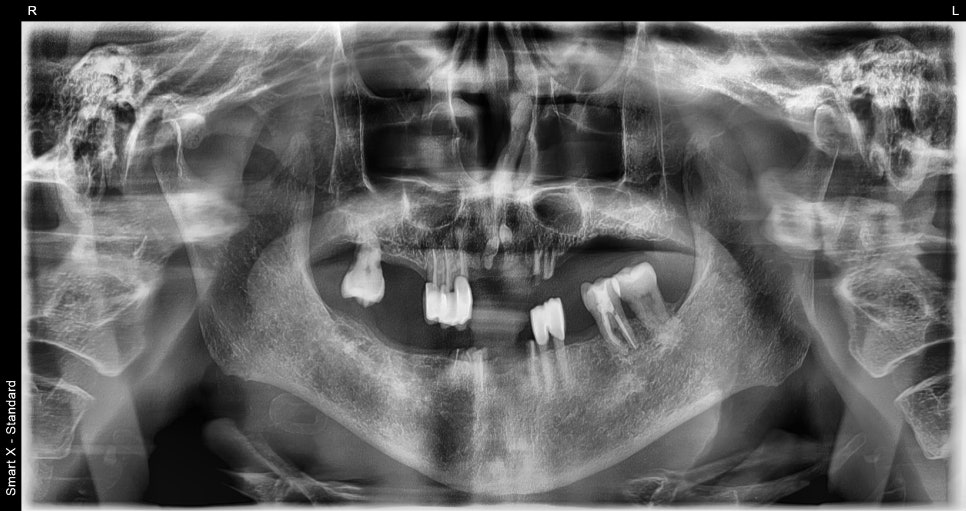

📌 틀니 치료 전 모습

– 상악: 치아

흔들림 심하고, 기존 틀니 적합 불량

– 하악: 부분틀니 고정력 부족, 잇몸 하중 부담